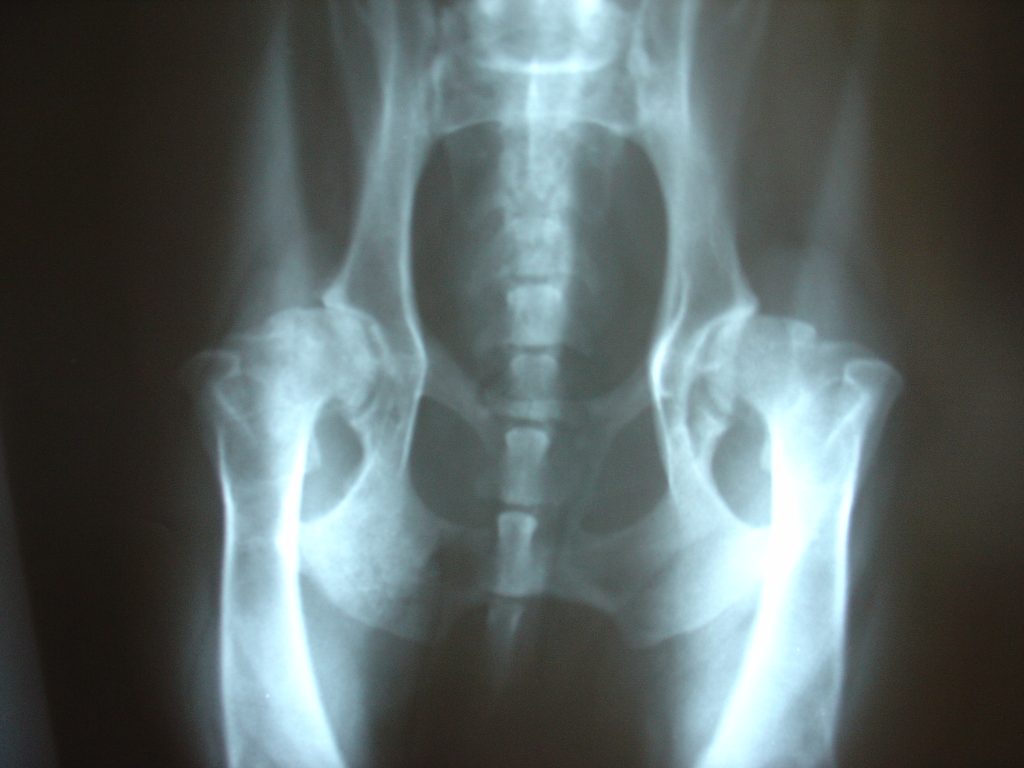

“Osteoarthritis will affect most of us during our lifetimes, many to the point where a knee joint or hip joint requires replacement with a costly and difficult surgery after enduring years of disability and pain,” Bay said. “Damage to the cartilage surfaces is associated with failure of the joint, but that damage only becomes obvious very late in the disease process, and cartilage is just the outermost layer in a complex assembly of tissues that lie deep below the surface.”